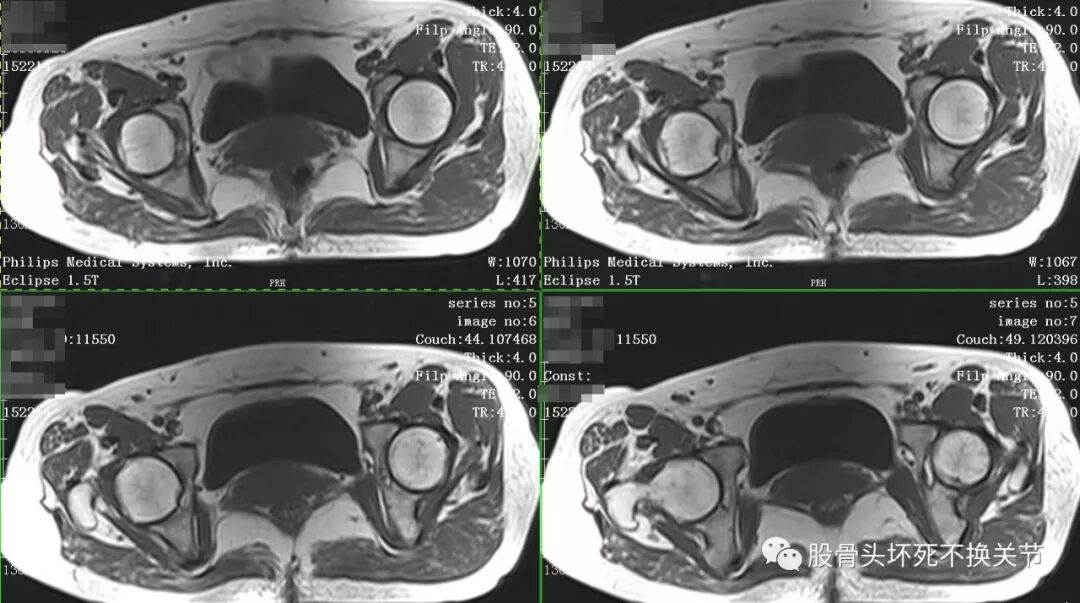

点击放大观看双侧髋关节核磁共振片:

核磁共振检查显示右侧股骨头周围一圈亮度均匀的白色信号,就是平常所说的关节积液。